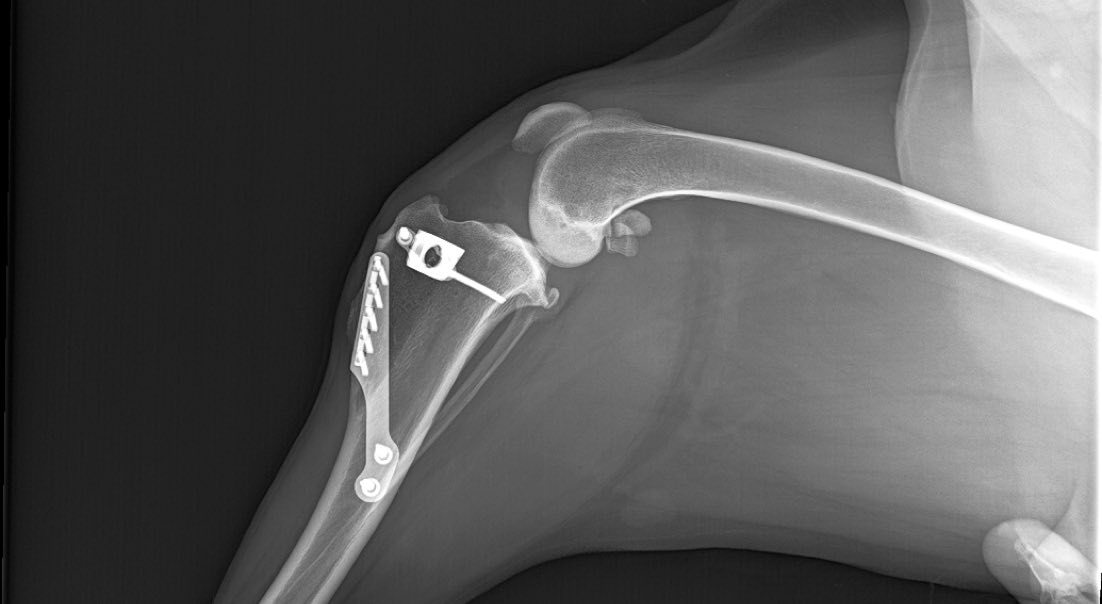

Die Tierärzte für die Region Baden-Baden und Achern betonen, dass es bei der Diagnose „Kreuzbanderkrankung“ Sinn machen kann, über eine frühzeitige Operation nachzudenken. Denn Tiere, die vor einem Abriss operiert werden, zeigen eine bessere Prognose. Dazu kommen verschiedene OP-Techniken zum Einsatz, die im „Kleintierzentrum Iffezheim“ individuell auf den Hund abgestimmt werden. Sein Größe, sein Gewicht, seine Beweglichkeit und sein Einsatzbereich spielen dabei eine Rolle. Bei Hunden über 25 Kilogramm rät die spezialisierte Tierärztin Dr. Wisniewski zu einer sogenannten Umstellungsosteotomie anstelle einer extra- oder intra-artikulären Stabilisationstechnik. Meist können die Tiere nach dem Eingriff am gleichen Tag wieder mit nach Hause.